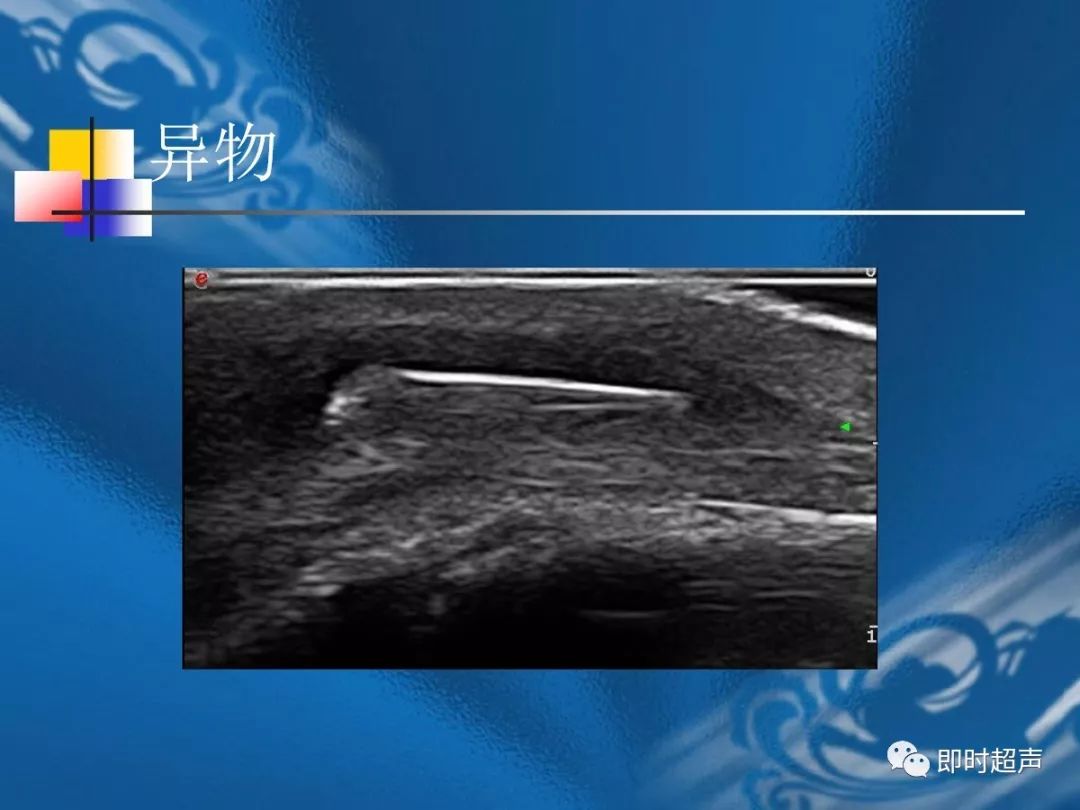

桡骨茎突狭窄性腱鞘炎